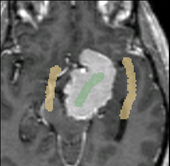

Caption 1

Caption 2

Caption 3

Caption 4